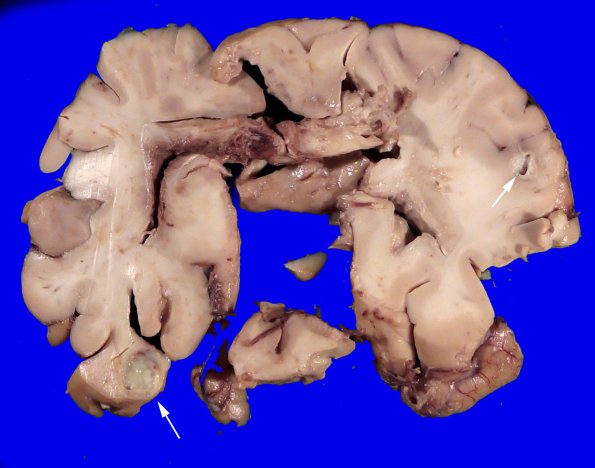

Other abscesses (arrows) are visible in this distorted soft brain.